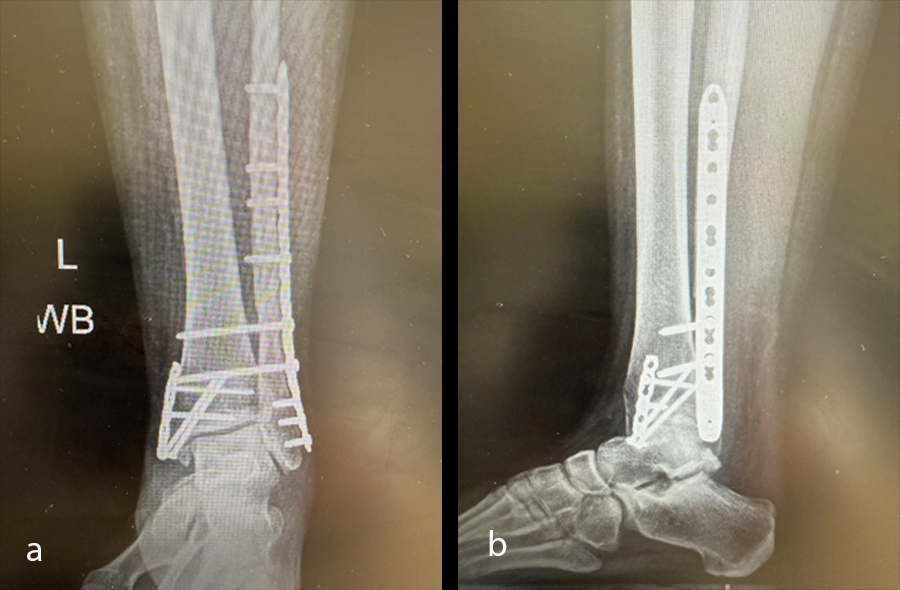

Case kindly provided by Andrew Sands, MD. New York Downtown Orthopaedic Associates, USA

A young adult had an accident, sustaining a trimalleolar ankle fracture with syndesmosis disruption (Fig 33).

Once the soft-tissue swelling had reduced sufficiently, the patient underwent open reduction and internal fixation (ORIF) surgery, with the VOLT™ Mini Fragment hook plate medially and the Small Fragment metaphyseal plate laterally. The syndesmosis was addressed with 4.0 mm screws (Fig 34). The surgery was uneventful and performed on an ambulatory basis.

At the 2-week postoperative follow-up, the splint was removed and the wounds assessed. The patient was then placed into a controlled ankle motion (CAM) boot and was advised to maintain nonweight bearing and start to gently increase range of motion in her ankle and hindfoot.

At the 6-week postoperative follow-up, the patient reported no pain and was advised to start progressive weight bearing with formal physiotherapy, and progressed from the CAM boot to a cushioned heel, rocker bottom shoe. X-rays taken at this time (Fig 35) showed good position of hardware and the fracture with signs of early healing.

At subsequent follow-up visits, the patient was doing well with full weight bearing and normal gait. The treatment plan is to remove the syndesmosis screws at 6 months postoperative or when convenient for the patient. As the screws are 4.0 mm, they are less likely to break. However, should screw breakage occur, the evidence [1] shows there is no disadvantage if they are removed from medial and lateral aspects of the ankle, or if the screw fragments are left in place.